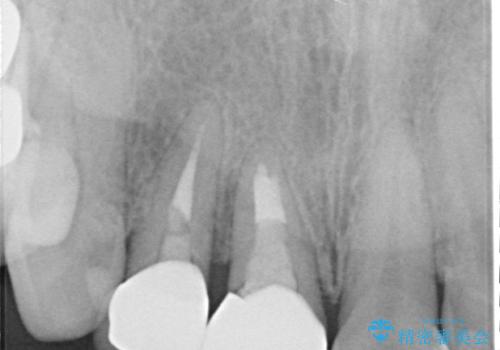

診察をしたところ、歯根に縦破折が認められ、抜歯が必要と判断されました。

抜歯、インプラント埋入、仮歯の装着が同時に可能な1DAYインプラントが適用可能と判断されたため、インプラントによる補綴治療を行うこととしました。

前歯のインプラント治療は、従来の抜歯から数ヶ月待機する手法では、骨造成や歯肉移植など付随の処置が多く必要となり、費用、期間、身体的負担のいずれもが多大となります。

抜歯時にインプラントを埋入することでそれらの負担を大きく軽減させることが可能です。